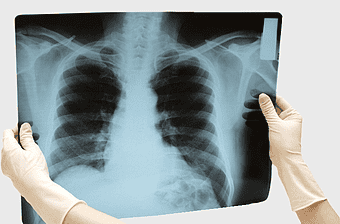

chest x-ray analysis, lung radiography, medical diagnosis service, rib health surgery, pulmonary imaging, thoracic radiology, respiratory care -

chest x-ray analysis, medical radiography, idiopathic pulmonary fibrosis diagnosis, lung disease imaging, respiratory health assessment, diagnostic imaging techniques, healthcare professional examining radiograph -